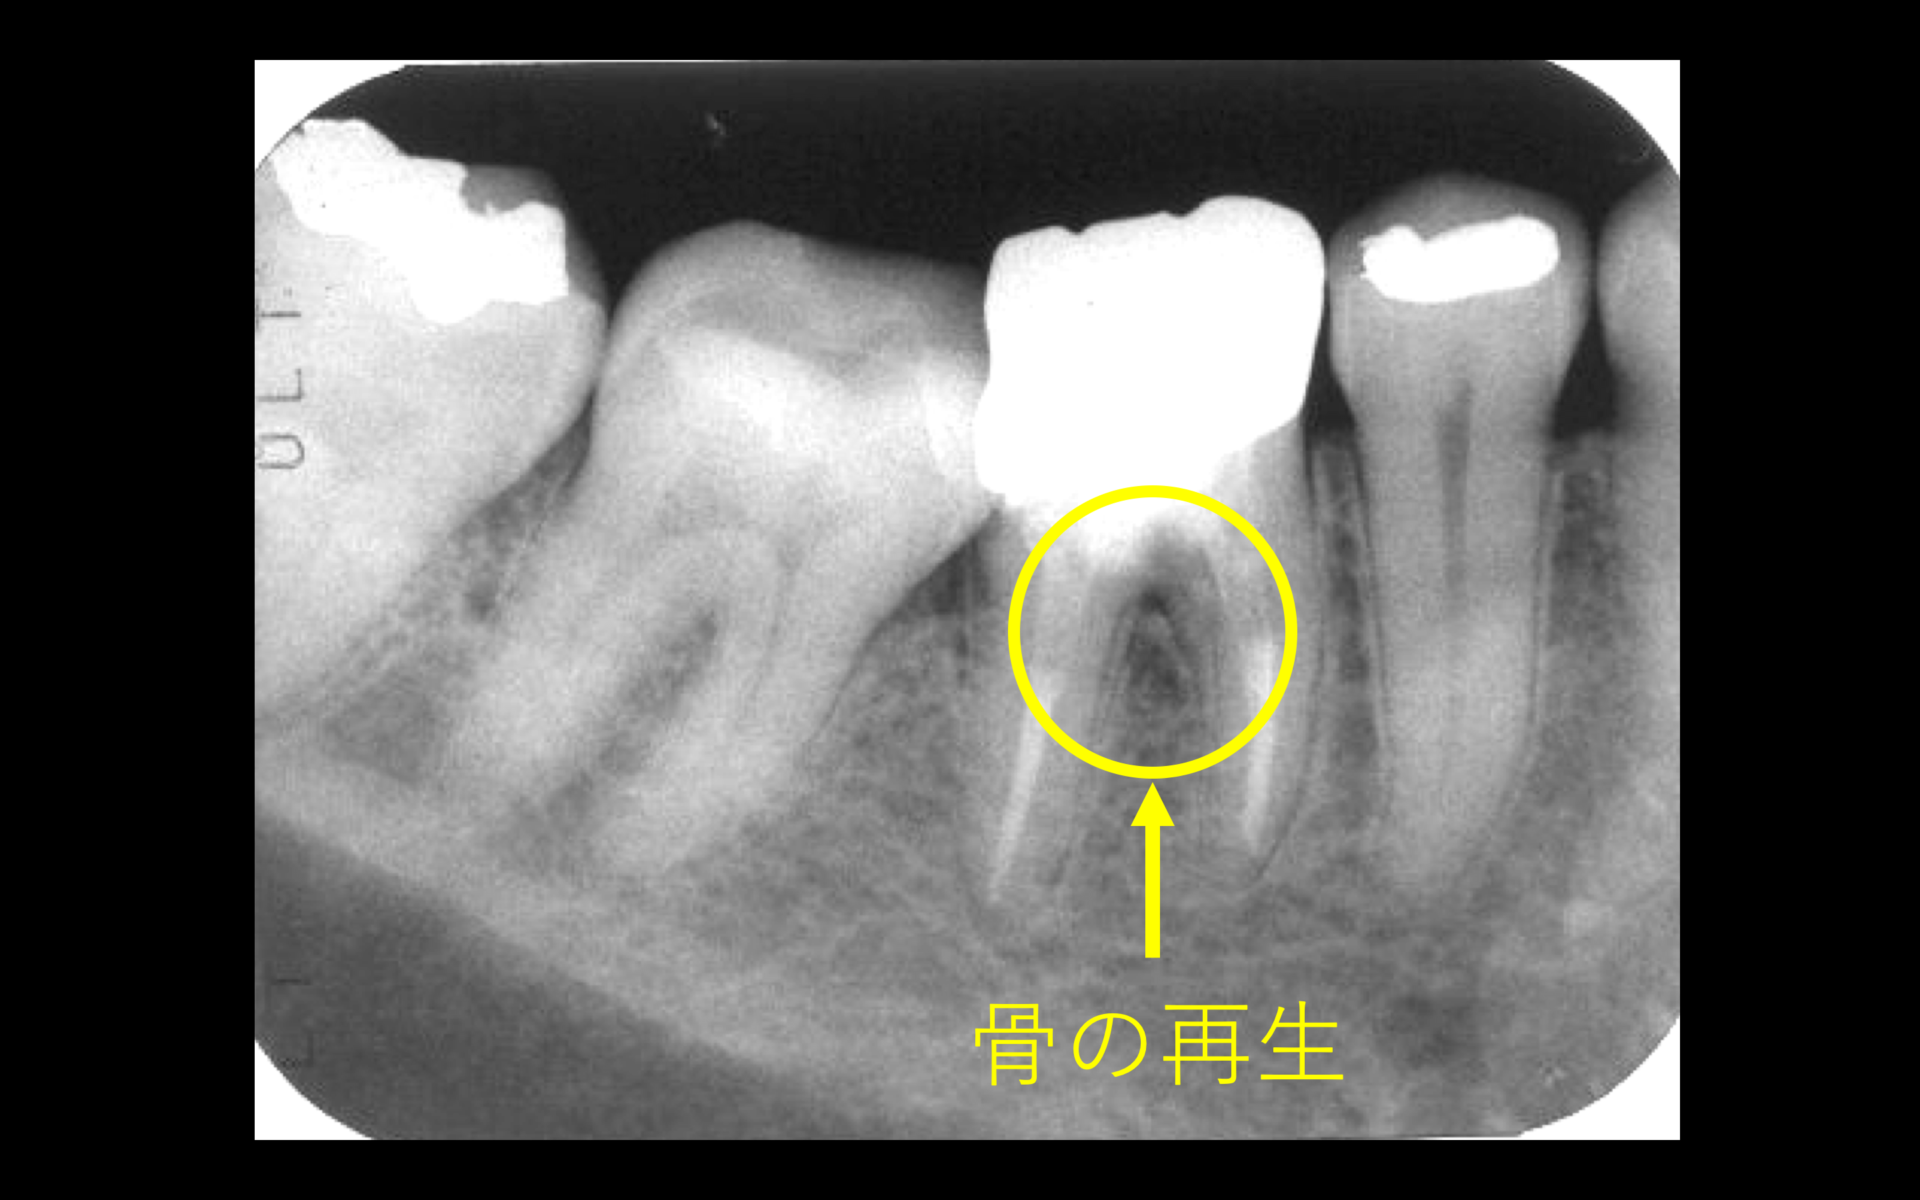

術後はレントゲン撮影により経過観察。初診時のレントゲンにあった黄色の円で囲っている黒い部分の病変は、経過を追うにつれ、病変が小さくなり、骨が再生されてきているのが分かる。歯周外科(再生療法)などは行なっておりません。

術後1年。レントゲン所見より黒い部分(病変)か消失し、完全に骨が再生されている(右図)被せ物はフルジルコニアクラウン(左図)